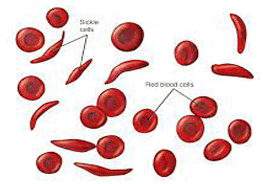

Pediatric Hematology